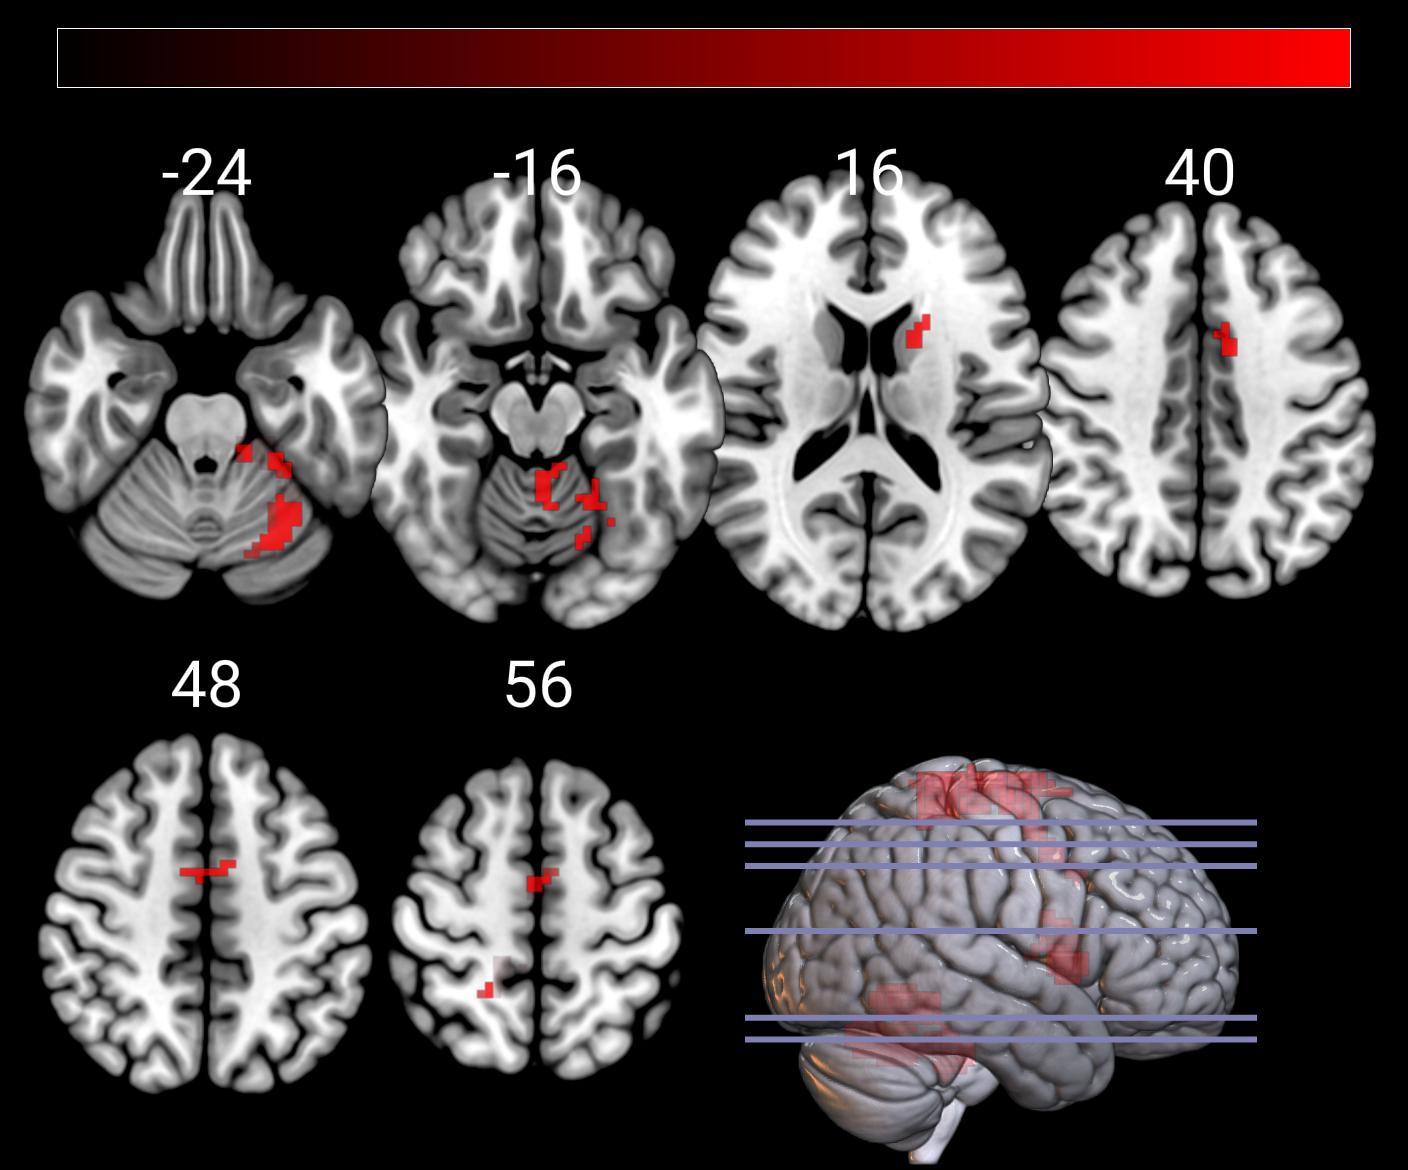

since I am using the latest release, I am not able to create smooth activation maps. Instead, I am getting the pixel of my SPM tmaps. Any idea how to solve this problem?

In the Layer panel, click "Options" and make sure "Load Smooth Overlays" is checked if you want the overlays to use trilinear interpolation when re-sliced to the background image. Otherwise, you will get chunky images.